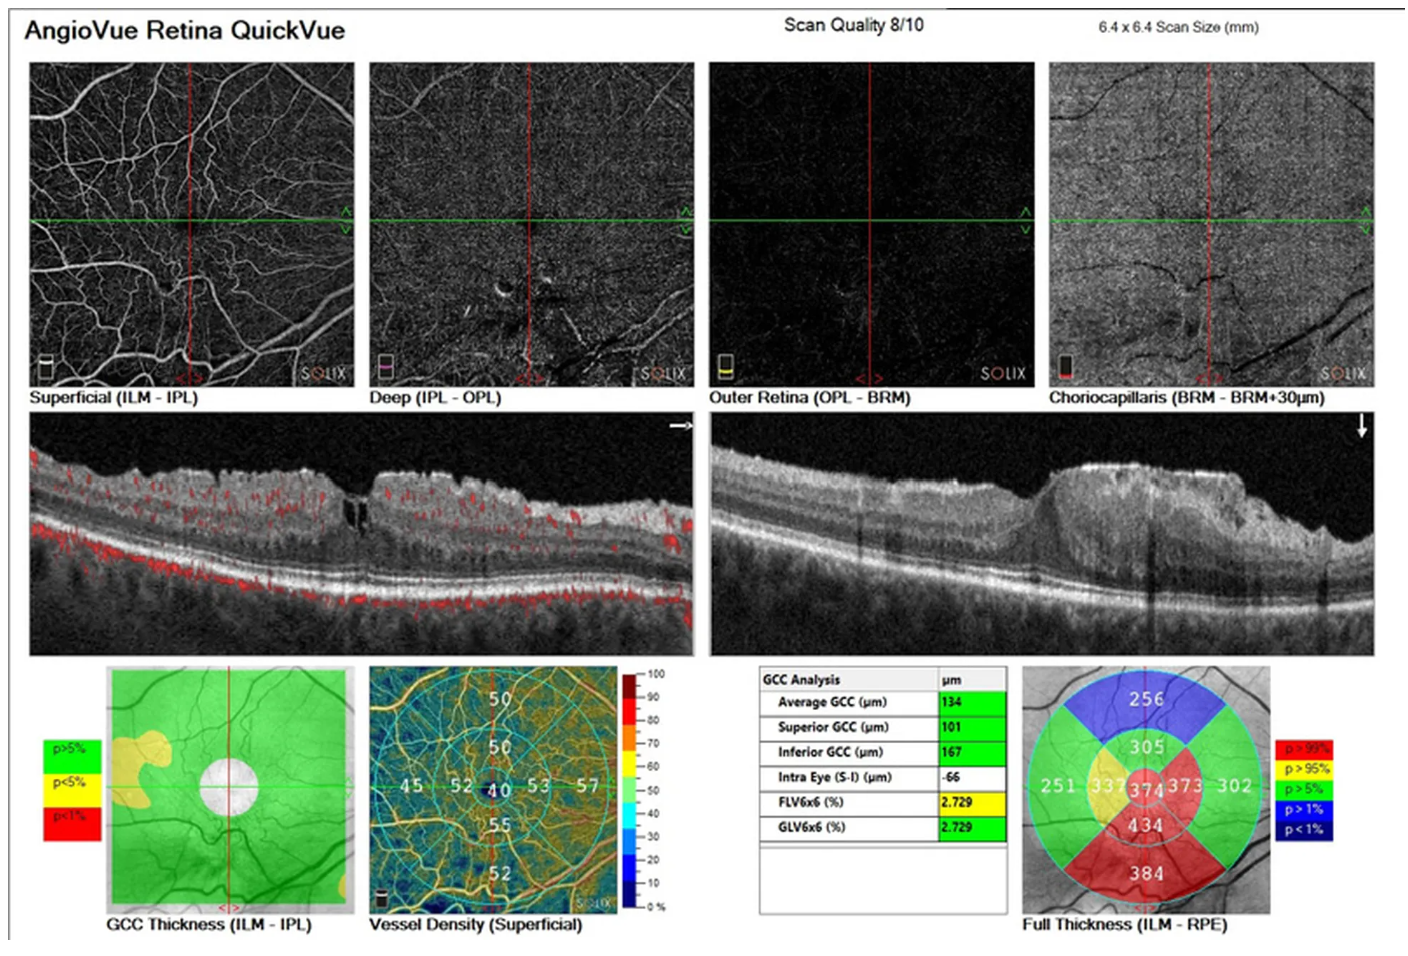

- Диапазон сканирования в режиме ангио-ОКТ — от 3х3 до 18х18 мм;

- Программа AngioAnaliticsTM для количественного анализа сосудов сетчатки;